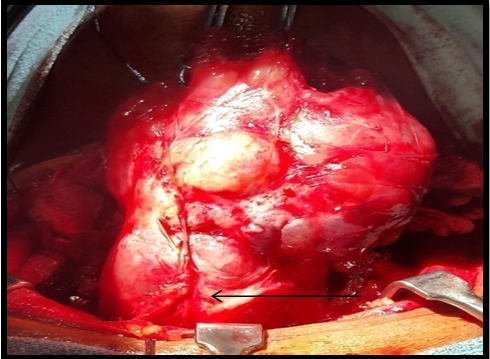

Figure 5C Retrosternal extension of the goitre with the lower pole at the level of thoracic inlet (arrow); being removed after gentle manipulation.

Figure 5D Ligating the thick thyroid ima artery. Note the engorged and thickened artery (arrow).